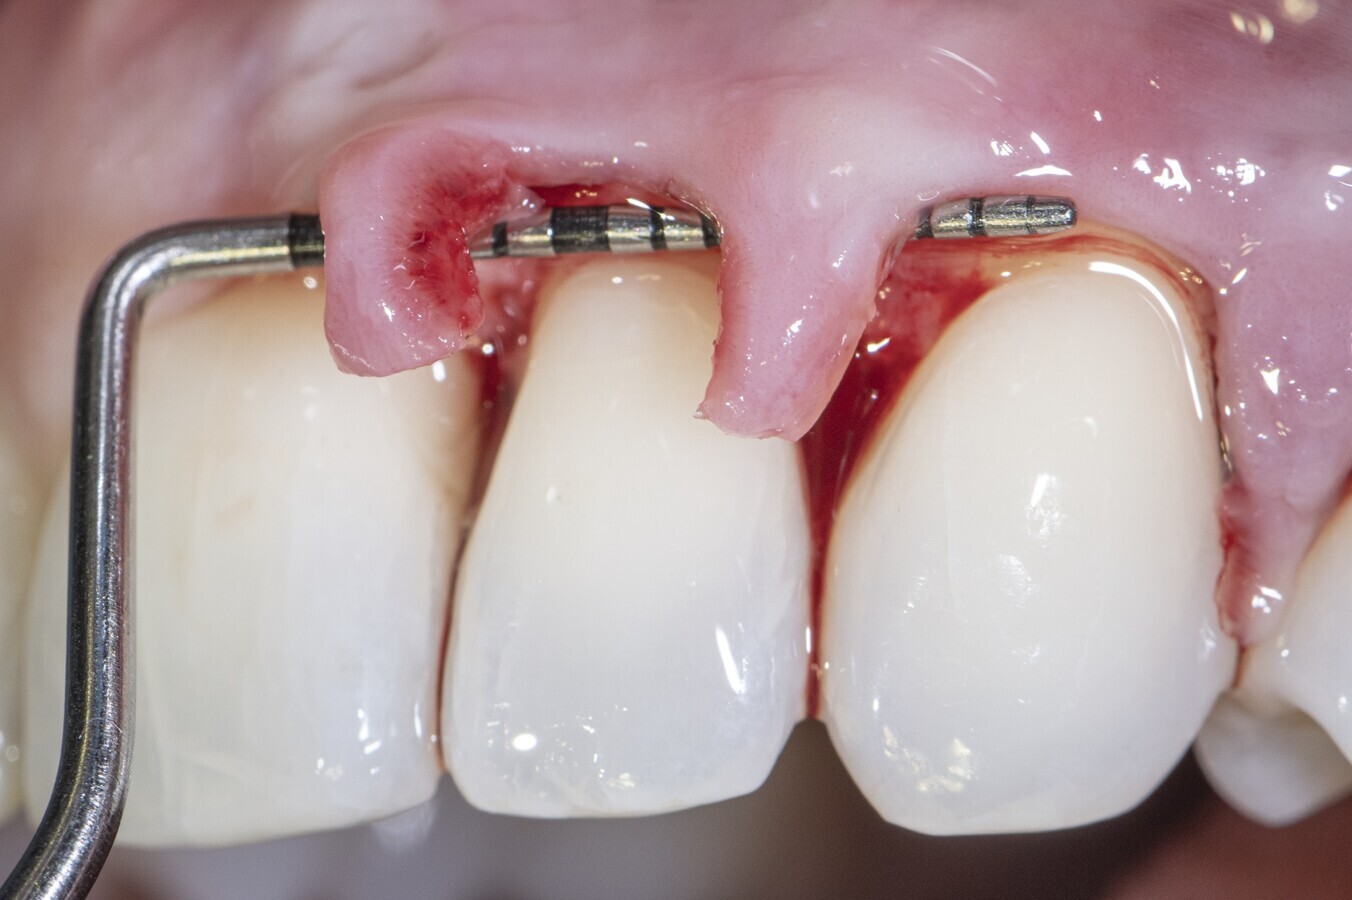

Dr Zuhr, your lecture at this year’s EAO congress focuses on surgical factors that can influence soft-tissue healing. Could you please give a brief overview of the key points you will cover in your presentation? First of all, attendees will learn that there are various categories of risk factors that influence soft-tissue wound healing outcomes, but only some of these factors can be controlled by clinicians. From there, we will concentrate on the risk factors that can be controlled, which are primarily related to ensuring optimal blood supply in the surgical field and maintaining the best possible stability of the wound after surgical intervention.

Soft-tissue healing is a critical aspect of periodontics and implant dentistry. Why do you believe it’s essential for clinicians to have a deeper understanding of the factors that influence soft-tissue healing? It’s all about wound healing. Success or failure in reconstructive periodontal implant surgery is primarily determined by soft-tissue wound healing outcomes. The ultimate goal, most of the time, is to achieve healing by primary intention. There are many examples of this: periodontal regeneration, successful guided bone regeneration, and soft-tissue reconstruction in areas of high aesthetic importance all rely on healing by primary intention.